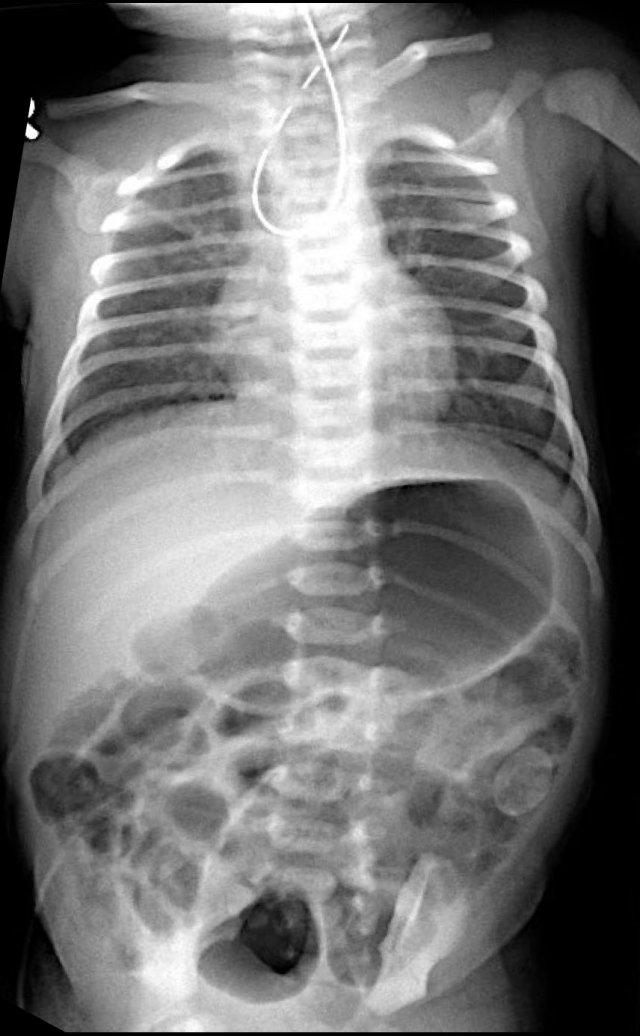

Các dấu hiệu bao gồm:

- Nhiều quai ruột non giãn

- Khí trong thành ruột (Pneumatosis intestinalis).

- Tràn khí ổ bụng (Pneumoperitoneum).

Chẩn đoán:

Viêm ruột hoại tử (NEC) có thủng ruột.